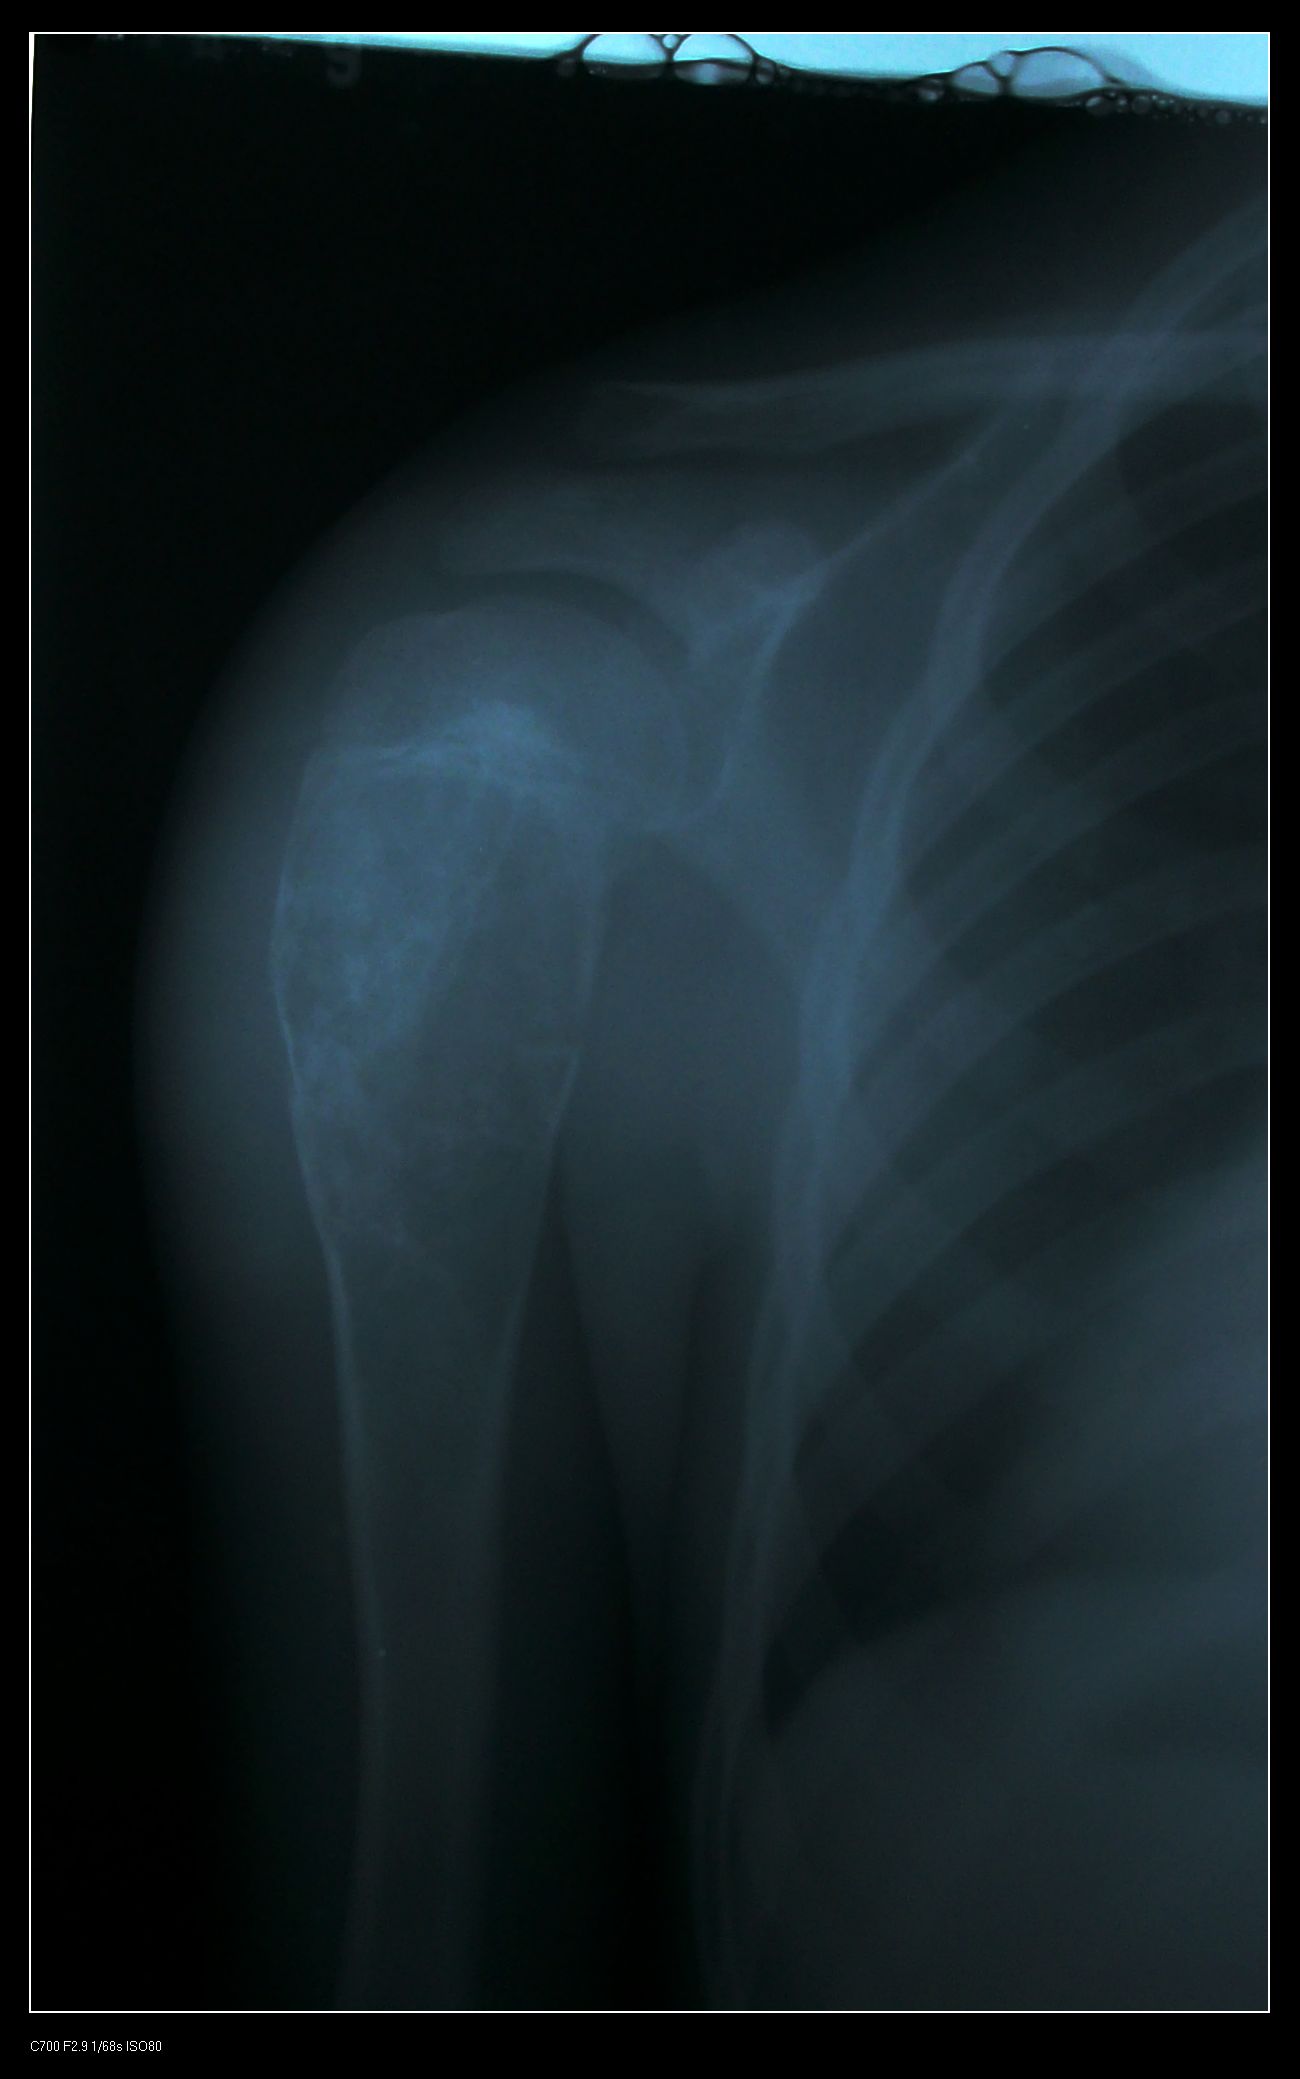

标题: X5828:骨囊肿

一小时前肩关节受外伤,一年前有外伤史

肱骨近端骨质呈多房囊状膨胀性改变,与骨干长轴方向一致,未突破骺软骨板,边缘见硬化,骨壳欠完整,可见“骨折片陷落征”,内见多个残留长短不一骨棘,软组织影无肿胀。

鉴别诊断:1、骨囊肿,典型发病年龄及部位,可见病理性骨折,较支持,不支持点是骨质膨胀较明显;

2、骨纤维异常增殖症:单骨多囊状破坏,外缘光滑,内缘毛糙波浪状,囊内外条索状骨纹及斑片状致密影具有特征性;

3、软骨母细胞瘤:骨骺部位偏心性病变,可跨越骺板;

4、abc,未突破骺软骨板,骨质膨胀;

5、软骨母合并abc。

考虑:骨囊肿合并病理性骨折可能性大,需排除骨纤、软骨母合并abc等。